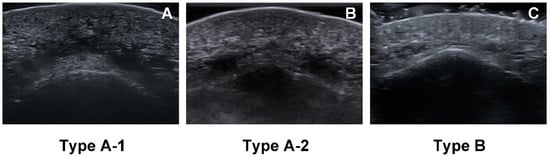

2.2. Location of the Mentalis Muscle

5.3. Depth of the Mentalis Muscle